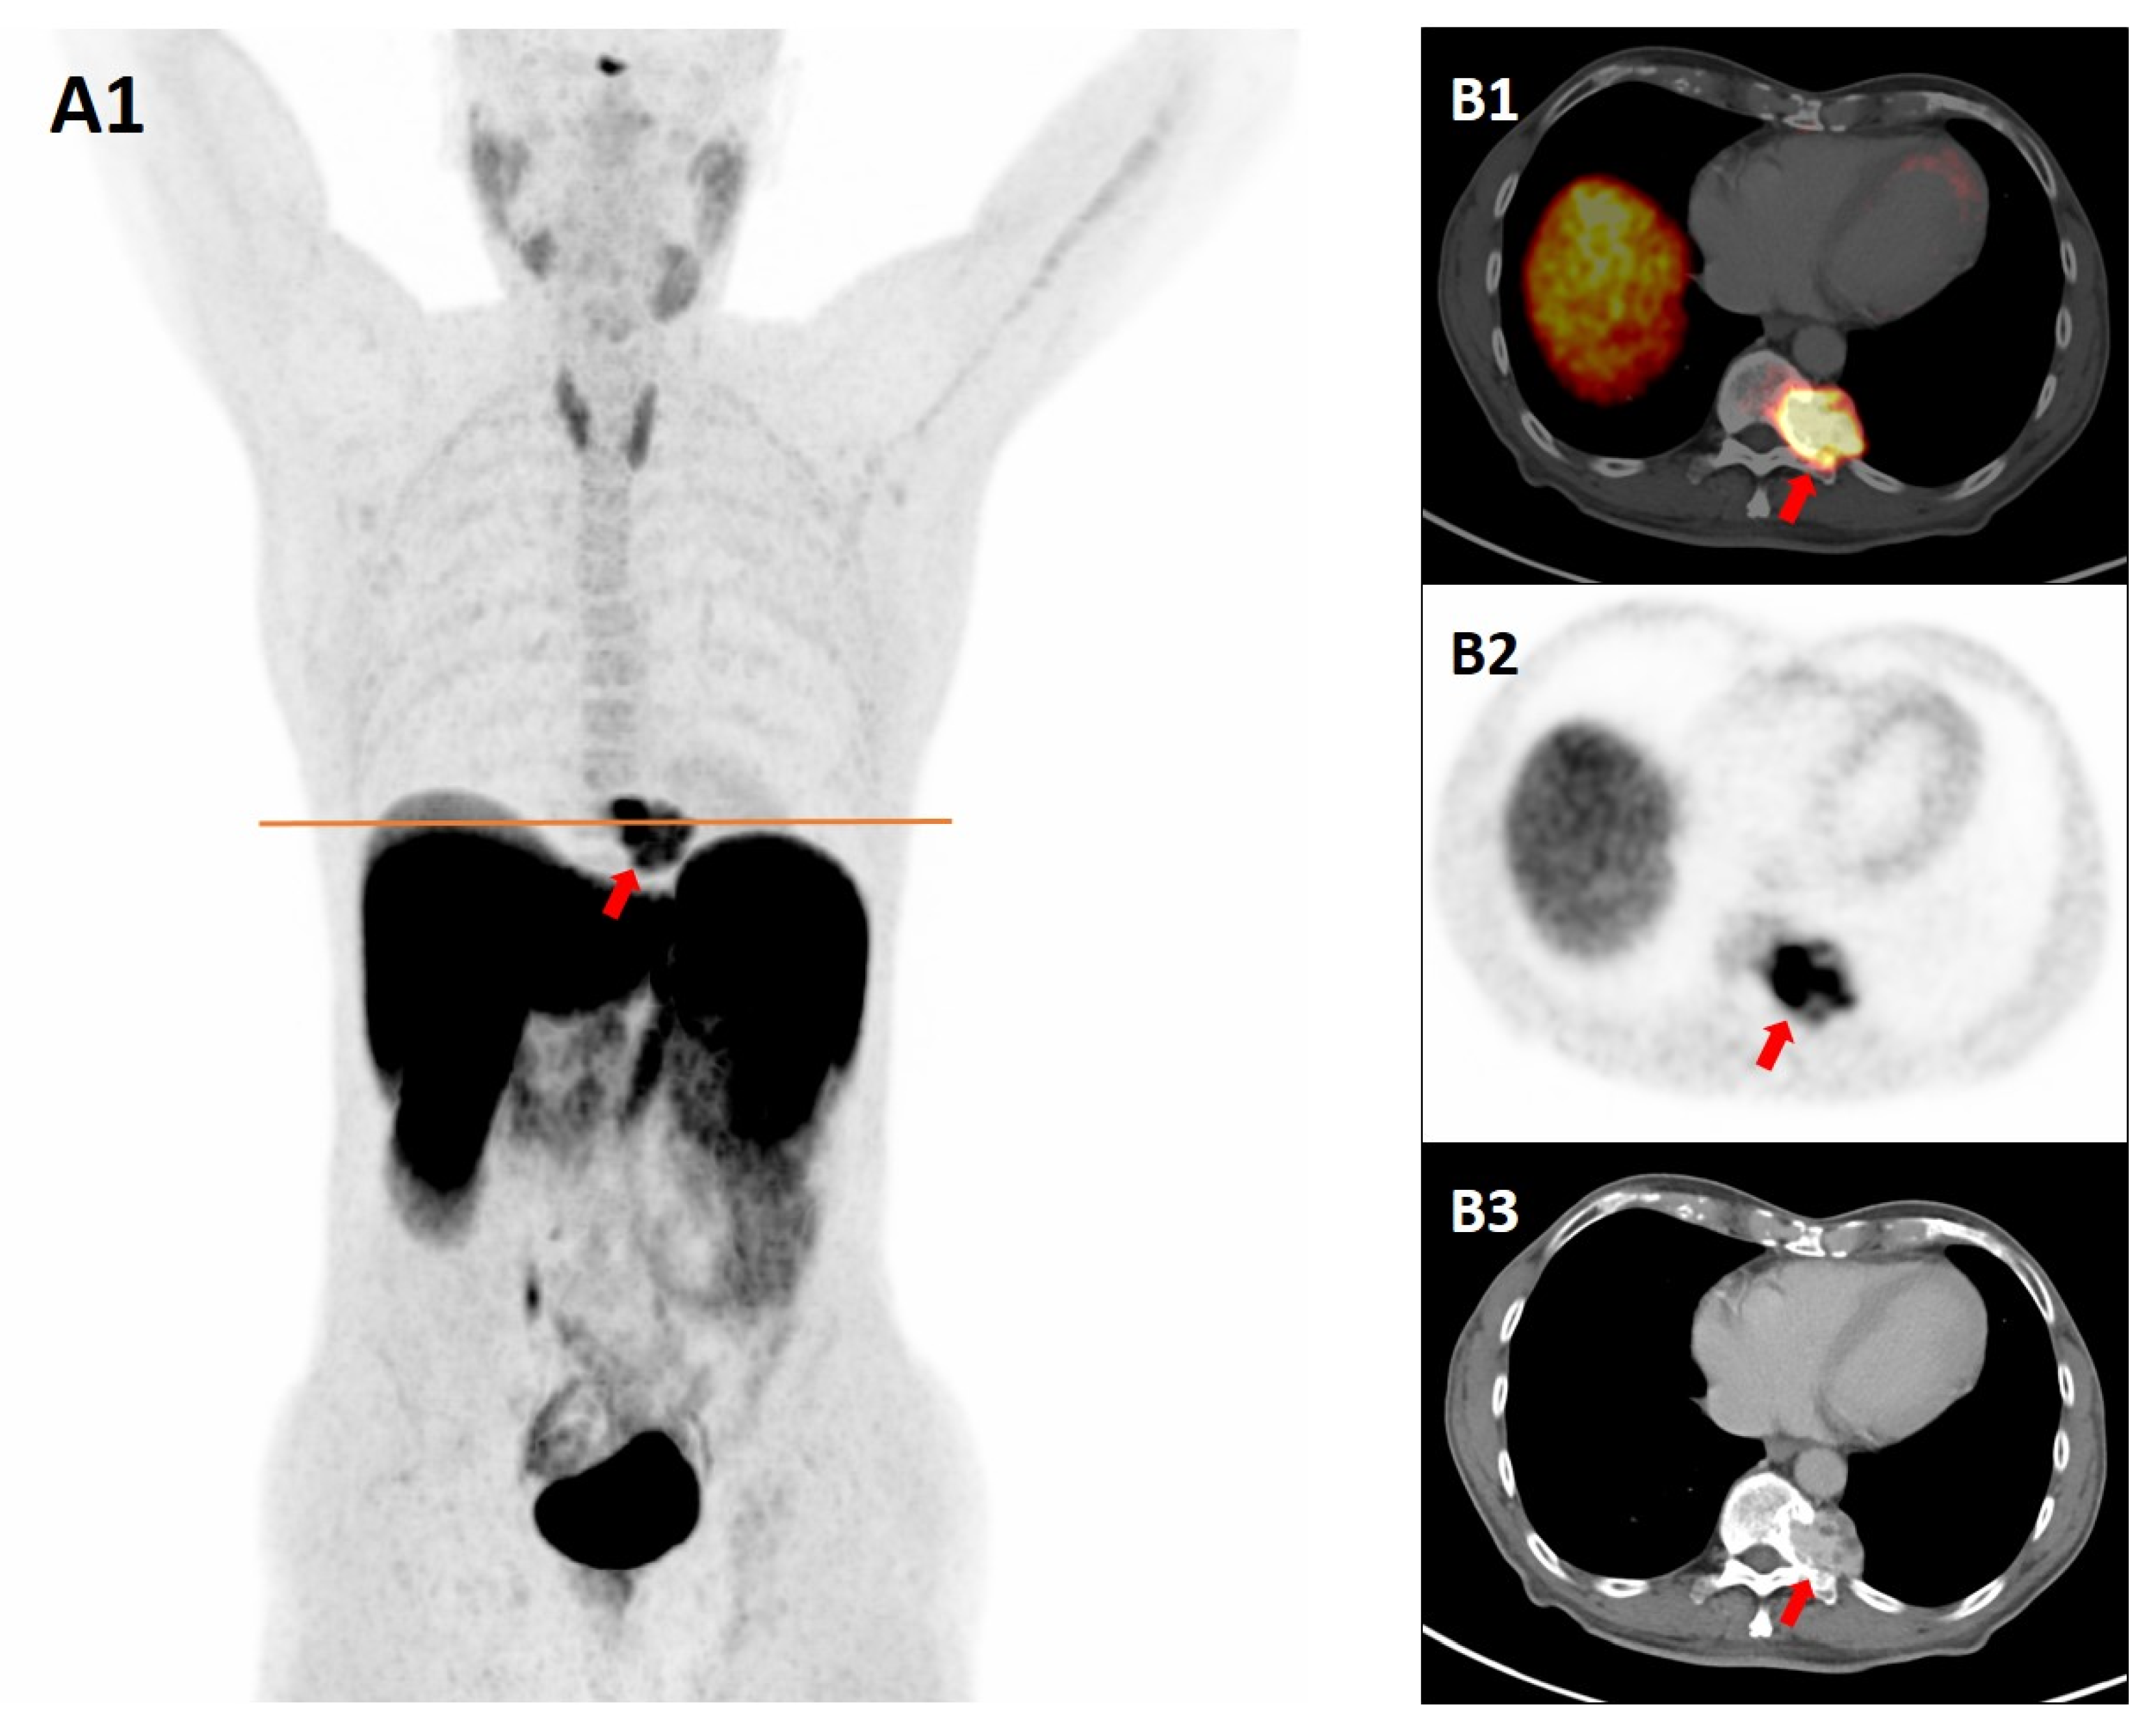

“Not All That Glitters Is Gold”: Paraspinal Cavernous Hemangioma Mimicking Paraganglioma on Somatostatin Receptor PET/CT